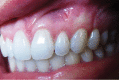

Gingival recession is an oral health problem that affects a large part of the population. Several treatments are suggested in the current literature; among them is the use of buccal fat pad grafting. The objective of this case report is to describe the treatment of a Miller Class I gingival recession using a nonpedicled buccal fat pad graft immediately after performing the surgery for buccal fat pad removal (bichectomy technique). First, bilateral surgical removal of the buccal fat pad was performed with the main objective of eliminating oral mucosa biting. The recipient site was prepared to receive a portion of the fat pad that was cut and macerated in a size that was sufficient to cover the recession. The patient was followed up at 15, 30, 60, and 365 days postsurgery, and the results showed an elimination of the oral mucosa biting and complete coverage of the gingival recession. It was concluded that the nonpedicled buccal fat pad graft is another option for the treatment of Miller Class I recessions.